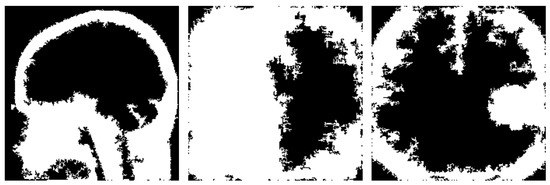

We can take a glimpse at the produced results for a specific image after using these two techniques in Figure 6.

Figure 6. Generated binary masks using Li’s and Otsu’s thresholding.

Jimaging 10 00232 g006